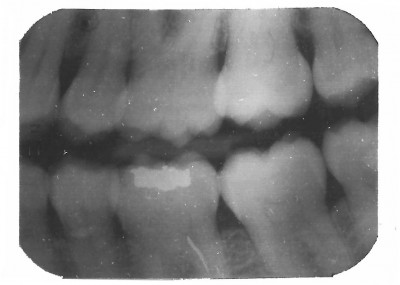

BW2

Bite Wing 2